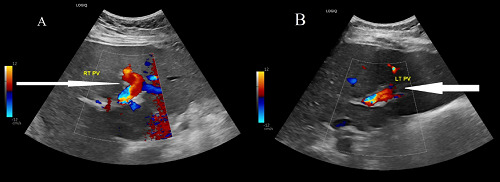

背景:肥胖和2型糖尿病(T2DM)是对全球医疗保健产生重大影响的现代流行病。胰高血糖素样肽-1受体激动剂(GLP1-RA) semaglutide是治疗tbl2DM和肥胖的一种新方法,但可能与静脉血栓栓塞的风险增加有关。病例介绍:本病例报告描述了一位59岁的tbl2DM女性患者,她接受了西马鲁肽来控制血糖水平,并经历了体重减轻的额外好处。在启动GLP1-RA的6个月内,患者出现腰痛,伴有恶心和口腔摄入不良。她没有已知的静脉血栓栓塞或血栓形成的危险因素,家族中也没有重大疾病史。她的体格检查未见明显发现。仅见轻度白细胞增多和嗜中性粒细胞增多。她接受了腹部计算机断层扫描,发现肝内门静脉血栓形成,但没有肝硬化或腹部恶性肿瘤的证据。口服抗凝药(利伐沙班)后症状得到改善。除Janus激酶2突变可能增加血栓形成的风险外,血栓检查结果为遗传性或获得性血栓形成阴性。结论:由于对减肥药的需求日益增长,GLP1-RA的使用正在增加。因此,医生在开始GLP1-RA治疗前更好地了解血栓形成的可能风险是很重要的。

Background: Obesity and type 2 diabetes mellitus (T2DM) are modern-day pandemics that have a significant impact on global healthcare. The glucagon-like peptide-1 receptor agonist (GLP1-RA) semaglutide is a novel treatment for both tbl2DM and obesity, but can be associated with an increased risk of venous thromboembolism. Case presentation: This case report describes a 59-year-old woman with tbl2DM who received semaglutide to manage glycemic levels, and also experienced the additional benefit of weight reduction. Within six months of initiating GLP1-RA, the patient experienced low back pain associated with nausea and poor oral intake. She had no known risk factors for venous thromboembolism or thrombophilia and had no history of significant illness in her family. Her physical examination revealed no significant findings. Only mild leukocytosis and neutrophilia were noted. She underwent an abdominal computed tomography scan, which revealed intrahepatic portal vein thrombosis without evidence of liver cirrhosis or abdominal malignancy. Her symptoms improved with oral anticoagulation (rivaroxaban). The result of thrombophilia examination was negative for inherited or acquired thrombophilia, except for a Janus kinase 2 mutation, which may increase the risk of thrombosis. Conclusions: The use of GLP1-RA is increasing due to the growing desire for weight loss medications. Therefore, it is important that physicians better understand the possible risks of thrombosis before initiating GLP1-RA treatment.